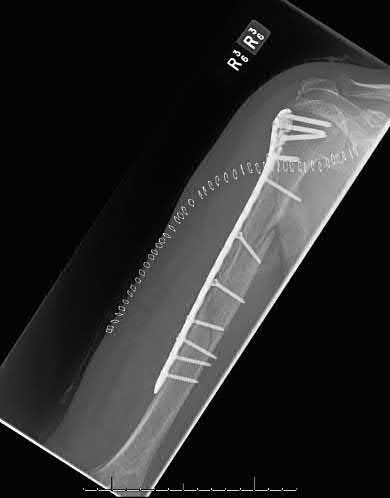

Question 9:

A 30-year-old male sustains a severe midfoot sprain. Radiographs reveal widening between the bases of the first and second metatarsals. The primary ligamentous stabilizer disrupted in this classic Lisfranc injury connects which two osseous structures?

Correct Answer: Medial cuneiform to 2nd metatarsal base

Explanation:

The Lisfranc ligament is the strongest ligament in the tarsometatarsal joint complex. It courses obliquely from the lateral aspect of the medial cuneiform to the medial base of the second metatarsal. It acts as the primary stabilizer of the second metatarsal base. Disruption results in the classic widening between the first and second rays, often with an avulsion fragment ('fleck sign').